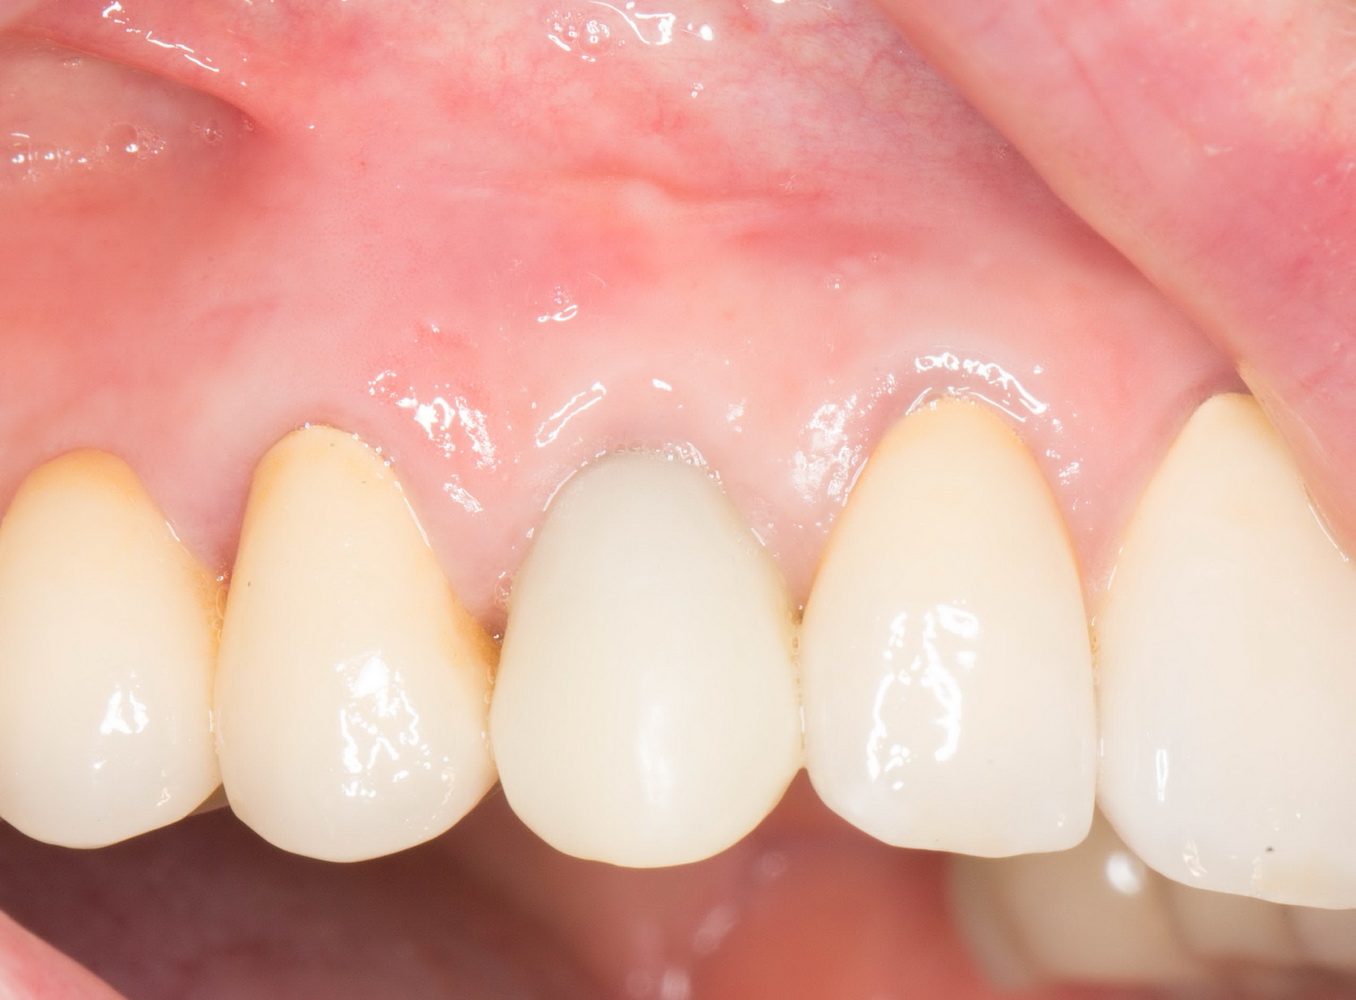

Через 3 месяца- внешний вид искусственного зуба:

Обратите внимание на состояние десны. Проведенные после установки импланта манипуляции позволили не только ее сохранить, но и увеличили объем. Формирование адекватных контуров и объемов слизистой оболочки, особенно в эстетически значимой зоне — еще одно назначение временных коронок на импланты. Все же, формирователи — штука стандартная, в то время как контуры десны как у разных людей, так и у разных зубов, свои — и под каждый зуб десну нужно готовить индивидуально.

Именно поэтому временное протезирование — важный этап всего лечения, который не рекомендуется пропускать. За редким-редким исключением.